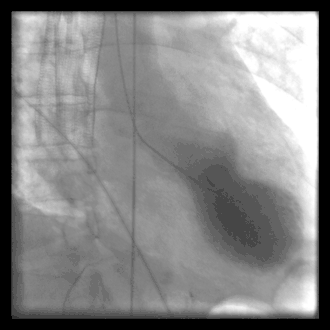

A common example of cardiac catheterization is coronary catheterization that involves catheterization of the coronary arteries for coronary artery disease and myocardial infarctions ("heart attacks"). Catheterization is most often performed in special laboratories with fluoroscopy and highly maneuverable tables. These "cath labs" are often equipped with cabinets of catheters, stents, balloons, etc. of various sizes to increase efficiency. Monitors show the fluoroscopy imaging, electrocardiogram (ECG), pressure waves, and more.

A patient undergoing a procedure where an 8 F introducer was placed in the right internal jugular vein using a 5F MAK access kit. A 7 F balloon tipped catheter was introduced via the venous sheath, the balloon was inflated and the catheter was advanced through the right heart chambers into the pulmonary capillary wedge position. Right sided pressures were obtained and cardiac output was measured using thermodilution.